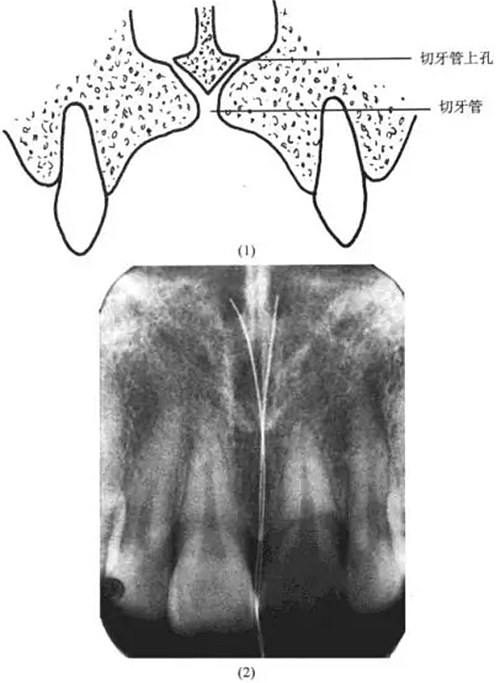

理由:解剖復(fù)習(xí)

切牙孔:在給片上常表現(xiàn)為一界限清楚的圓形、卵圓形密度較低影像,根尖片上切牙孔的位置可位于中切牙牙根之間,靠近牙槽嵴或在根尖平面。

切牙管:終于切牙孔,可見于中切牙的根尖片上。

切牙管上孔:共2個(gè),位于鼻前唇底,與鼻中隔鄰接,根尖片上切牙管上孔的影像可能投射到任何切牙的根端,因而有時(shí)可誤認(rèn)為根尖周病變(圖13-5)

上述病例的診斷可據(jù)此及牙髓活力存在而確診。